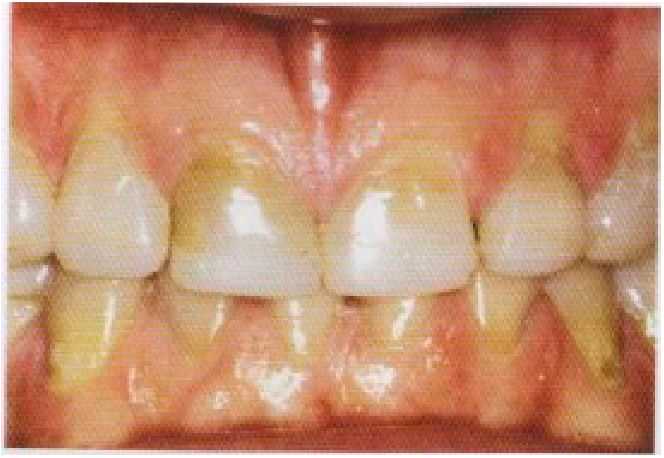

. Если замещения утраченных зубов временными частичными съемными протезами не требуется, то предпочтение отдается применению обычных адгезионпых композиционных пломбировочных материалов, обеспечивающих одномоментное увеличение высоты лица (рис. 7-6).

Рис. 7-6. Использование обычного композиционного пломбировочного материала лля восстановления приемлемого внешнего вида и окклюзионной высоты лица без применения частичных съемных протезов. (С разрешения Мг.К. Топез.)